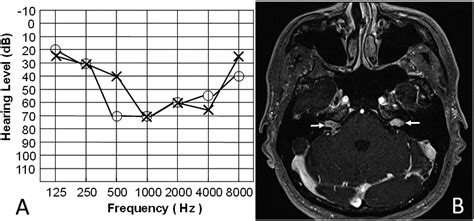

Hearing loss is measured in decibels (dB) across various frequencies. Medical professionals use the following table to categorize the impact of Bilateral Sensorineural Hearing Loss on an individual’s daily life.

The diagnostic process is non-invasive and painless. It typically starts with an otoscopic examination to ensure there is no wax blockage or structural issue in the outer ear. Following this, the audiologist will perform pure-tone audiometry to map out your hearing thresholds in both ears. Bone conduction tests may also be conducted to verify that the middle ear is healthy, thereby confirming the “sensorineural” nature of the loss. These steps are essential to rule out other medical conditions before proceeding to auditory rehabilitation.

• bilateral sensorineural hearing loss audiogram